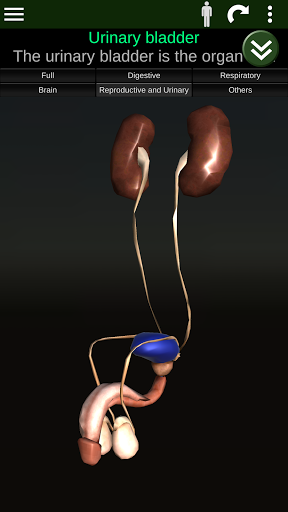

Toont een 3D-anatomisch model van de belangrijkste organen van het menselijk lichaam en een beschrijving van elk orgaan.

* Voortplantingssysteem, dat de mannelijke en vrouwelijke voortplantingsorganen omvat.

* Gemakkelijk te openen en te navigeren (zoom, 3D-rotatie).

* Vergelijk mannelijke en vrouwelijke organen.

Deze app is ontworpen als aanvulling op de studie van anatomie in verschillende onderwijs-, gezondheidszorg- en culturele omgevingen.